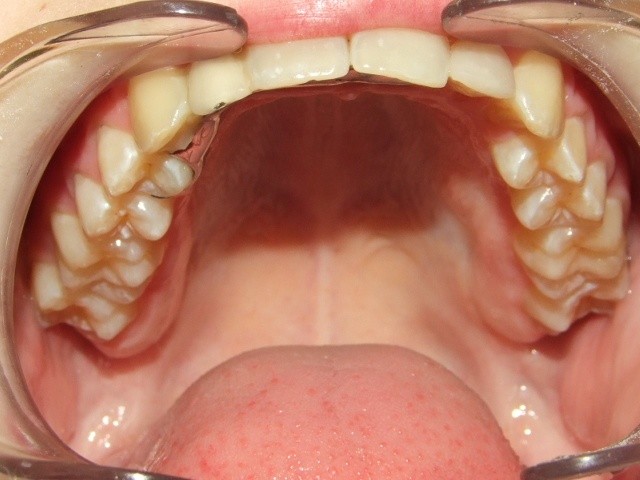

Maand 1-6: In de bovenkaak Bonded Hyrax, FaceMask

In de onderkaak volledig slotjes/brackets

TransForce met behulp van banden

Maand 7-26: Brackets en banden in bovenkaak en onderkaak

Expander in de bovenkaak

Retentie fase: Invisable Retainer en C-C- Bar

Leeftijd bij retentie fase: 13 jaar